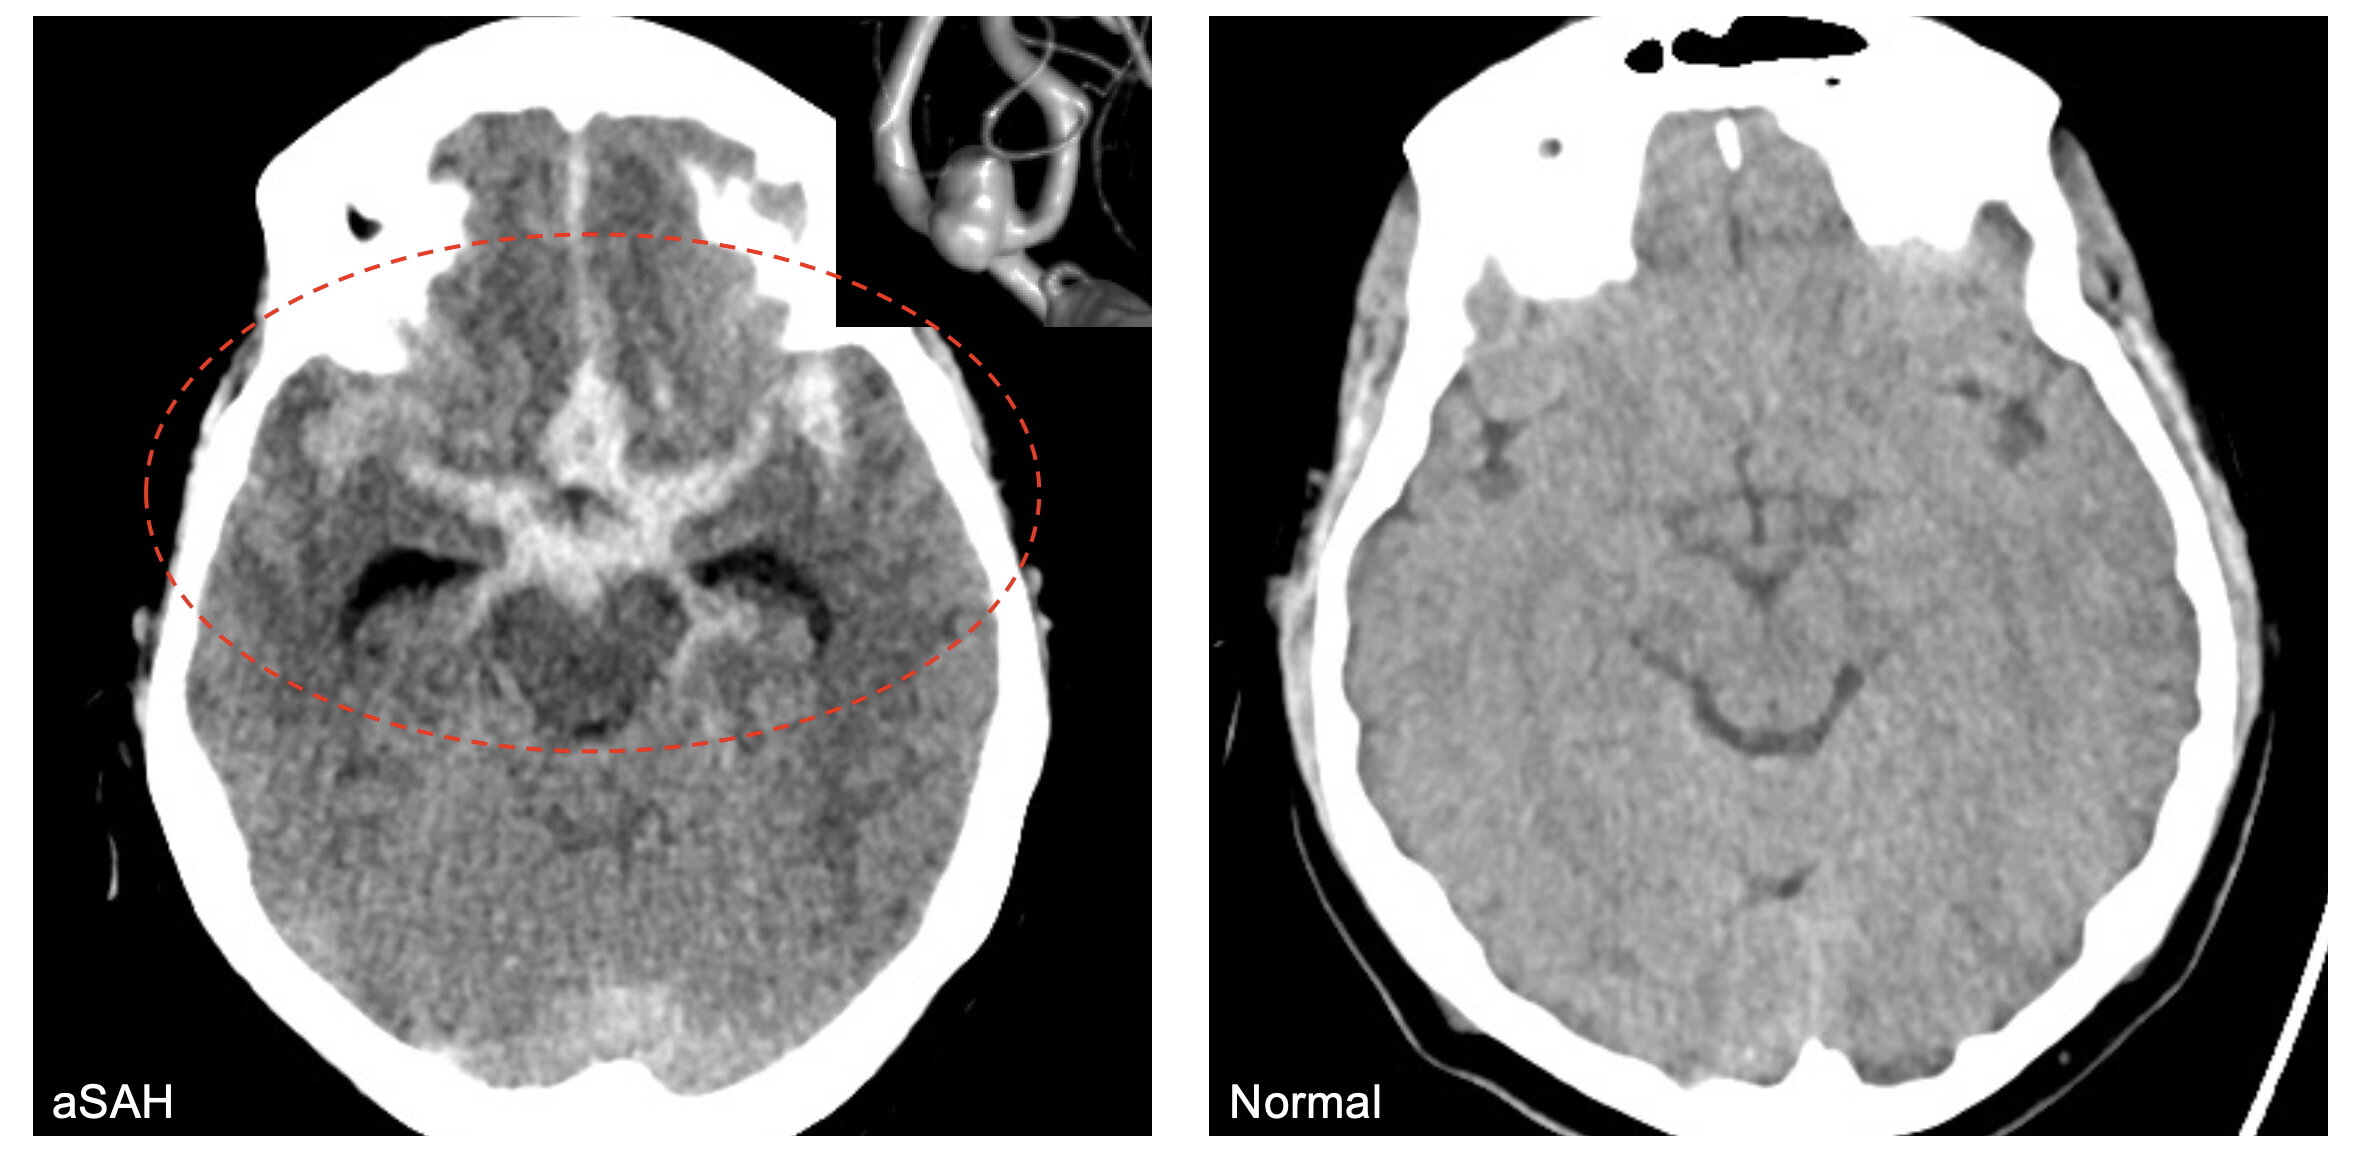

Les chercheurs de l’Université de l’Utah en santé ont documenté une association entre l’exposition à la pollution atmosphérique et un rare type de saignement dans le cerveau. Une hémorragie sous-arachnoïde anévrismale, ou ASAH, peut endommager suffisamment les tissus cérébraux pour laisser les patients paralysés ou dans le coma ou provoquer la mort.